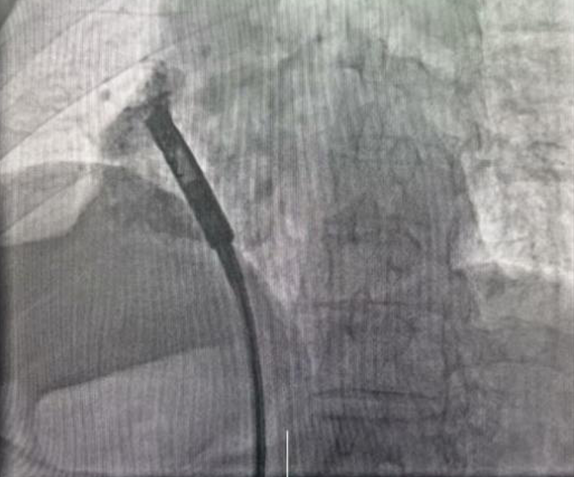

手术团队通过患者股静脉这一微创路径,将仅有传统起搏器十分之一大小的新型无导线起搏器精准输送至右心耳,利用其特有的用于心房起搏的双螺旋设计,起搏器被牢固地锚定在右心耳基底部。整个手术过程顺利,耗时22分钟,术中及术后参数测试均显示起搏器工作状态良好。

RAO 30°猪尾造影,目标植入位点右心耳基底部位置。